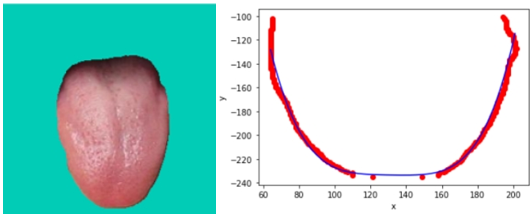

首先是要将舌象图片进行舌体分割(参照计算机视觉智能中医(三):基于Unet模型的舌头舌体图片分割)

舌体胖瘦分析的主要的对象是中下舌位,上舌位会影响分析的准确性,因此取舌体轮廓标记点的下0.75舌位。示意图如下图所示:

对下0.75舌位标记像素点进行舌体轮廓的多项式曲线拟合。由于分析的是曲线的“胖瘦”,因此多项式曲线的奇数次项影响较小,且项数较大较好。权衡模型的运行效率,中e诊采用4次项多项式曲线拟合。进行多张图片拟合的确定系数(R-square=SSR/SST)为0.82~0.95,说明4次多项式曲线拟合效果较好。舌体轮廓4次多项式拟合示意图如下: